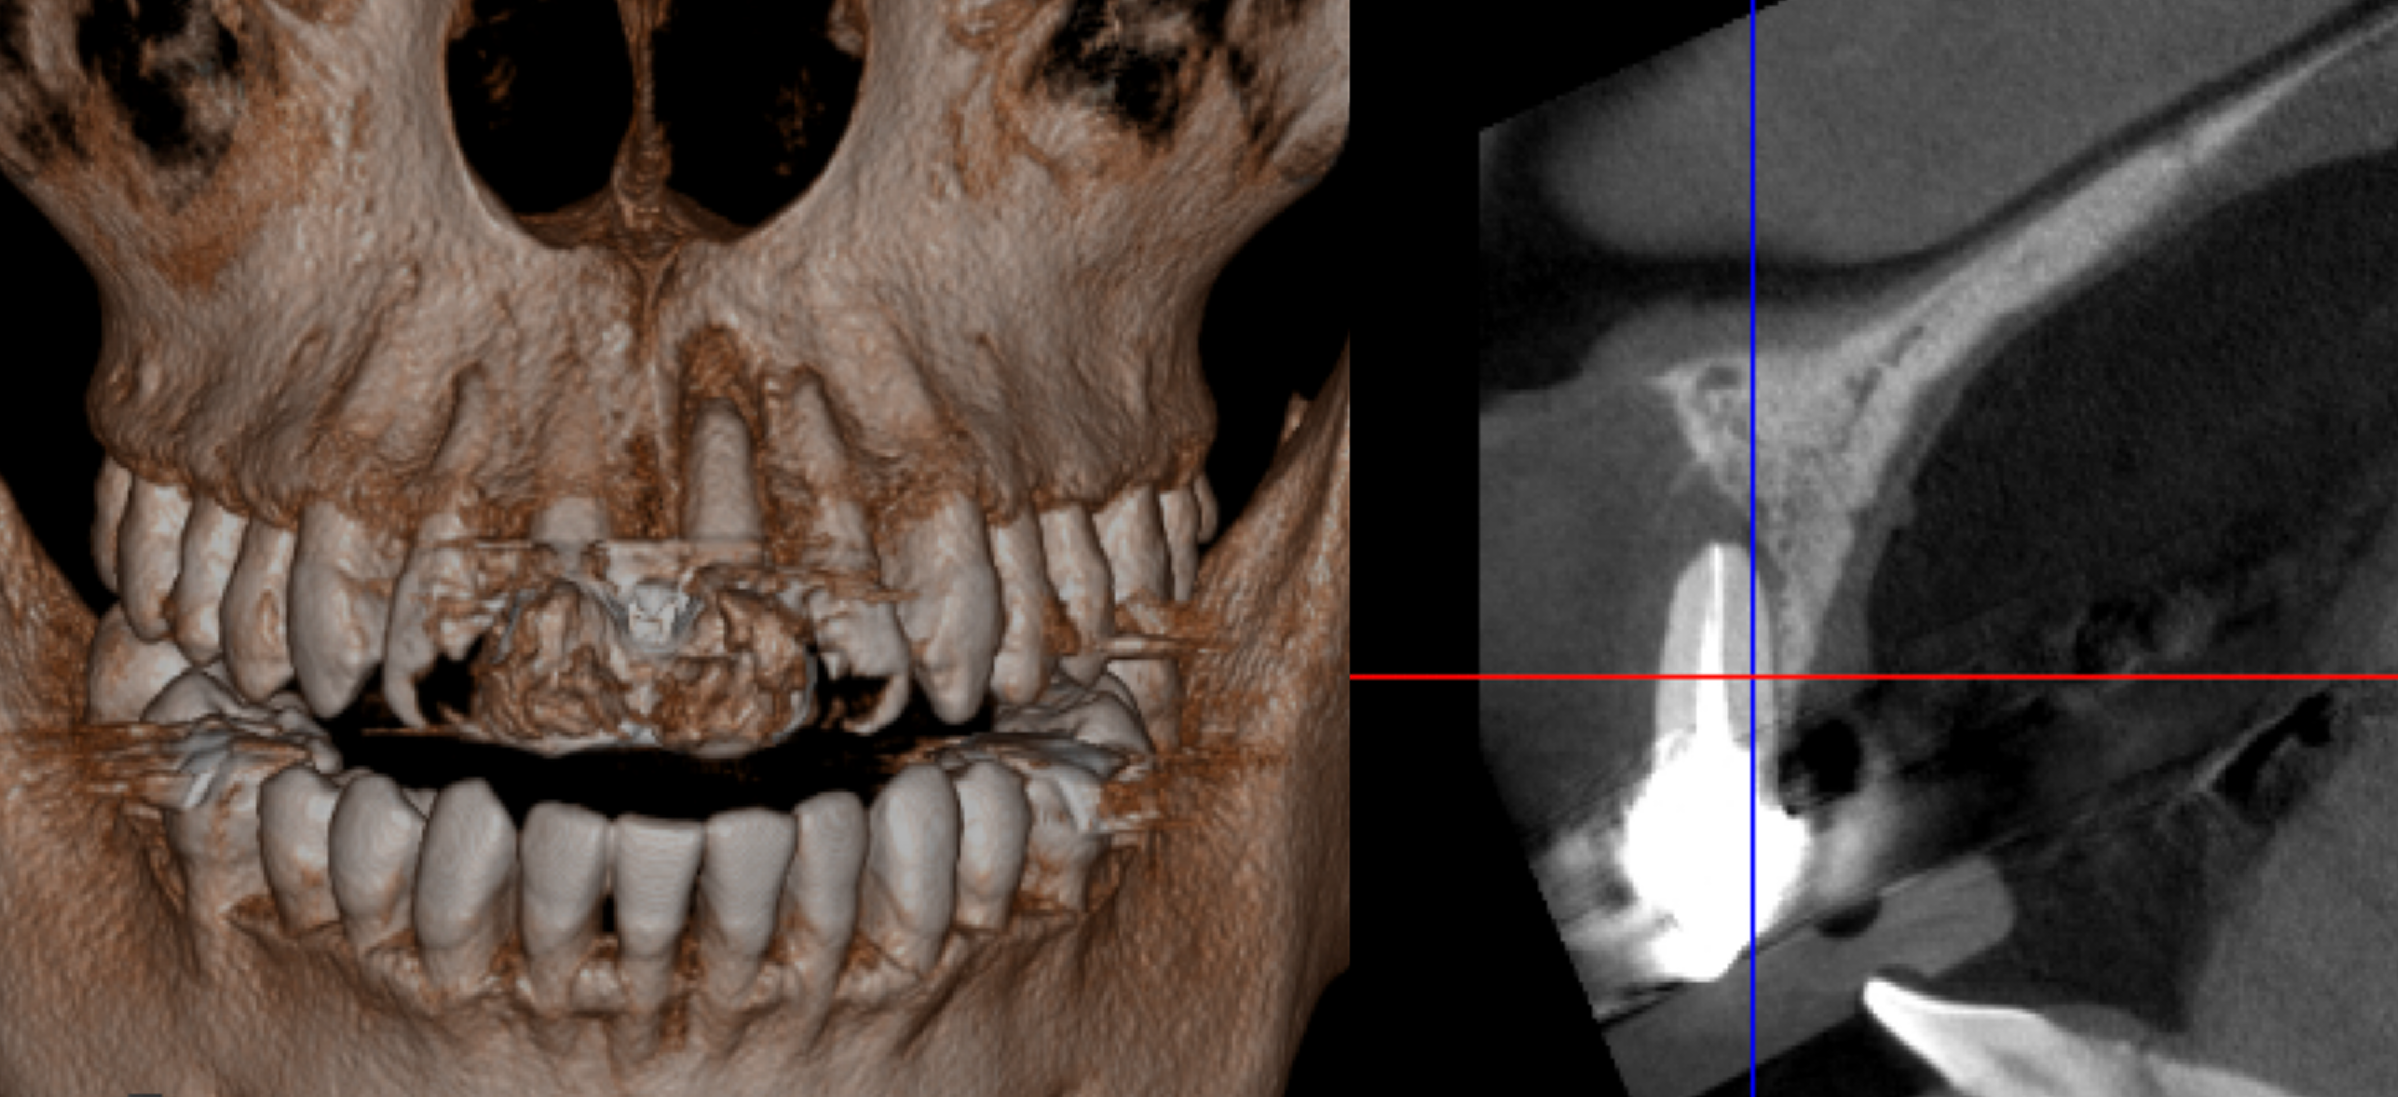

デジタルシミュレーションを駆使したことで、術前の「生理的咬合である」という診断に基づいた精密な治療計画の立案が可能となりました。

治療期間はかかりましたが、計画通りに全顎の機能回復を達成し、「安心して噛める」状態を取り戻すことができました。

治療は完了しましたが、この状態を長く維持するため、今後はメンテナンスでの噛み合わせのチェックが非常に重要となります。

行った治療

最後は下の前歯だけが残る、この状態の患者様はよく見かけます。この患者様の場合、歯がなくなった原因が「不適切なアンテリアガイダンス」です、これを改善しない限り、入れ歯にしろ、インプラントで歯を作るにしろ、ご自身の歯が抜けてしまったように壊れてしまうのは当然です。

まず一番必要なのは、下の前歯の傾きを適正なものにし、「適切なアンテリアガイダンス」を作ることです。今回、下の前歯を全て残した状態で矯正治療により適切な位置に歯を動かすか検討しましたが、歯を支える骨の問題で矯正治療では対応できず、犬歯以外は抜歯しBrにて適切な前歯の形を作る治療計画を立てました。

理想は歯も残して病的な位置を改善させたいのですが、今回は残念ながら無理でした。ただ、病的な位置をそのままにすることで安定した状態が作れません。歯より「安定して噛める状態」を優先するか、病的な位置の歯を残し、安定を求めずに治療を繰り返しながら過ごすのか、これは患者様との相談上決定するようにしております。

今回は抜歯し「安定して噛める状態」を作ることで同意されたのでこのような治療を行なっております。下の歯は入れ歯より強固なインプラントを選択し、上は総義歯を使用し治療をいたしました。